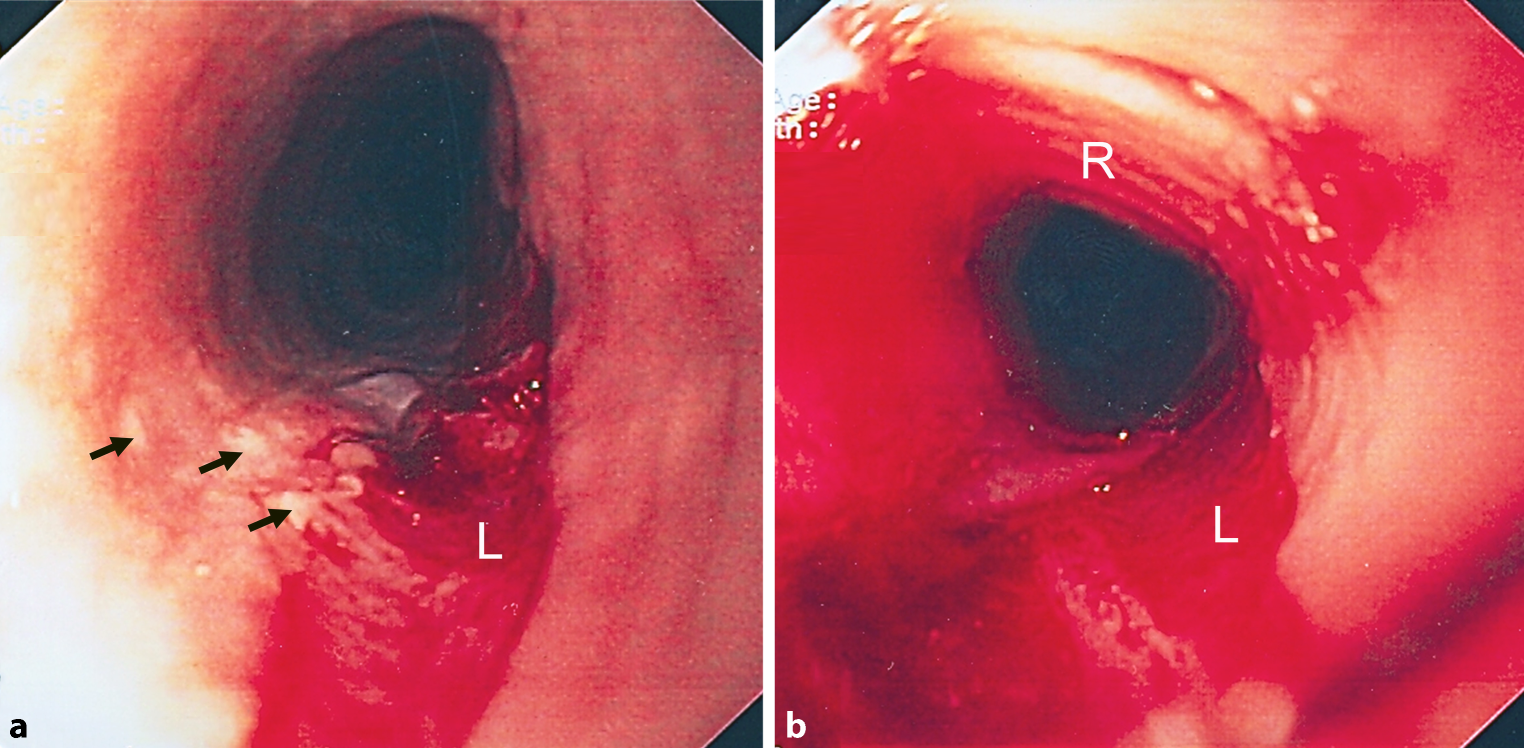

When the discussed patient came to the emergency room, the diagnosis of food impaction was confirmed by esophagogram (Fig. 1). After the bolus had been removed by means of a rigid esophagoscope, the patient had a normal barium swallow without signs of achalasia.

Fig. 1

Images from a barium swallow (cineesophagogram) with a complete hold-up of barium in the proximal esophagus and b free passage of barium into the stomach after removal of the bolus, without evidence of perforation

Manometry revealed a slightly prolonged duration of swallowing with minimal nonspecific alterations, probably due to mild esophageal spasm. On endoscopy, multiple areas of the esophagus appeared like crepe paper with thickened mucosa, there were white plaques, longitudinal furrows and minimal circular rings (Fig. 2). Biopsies were taken from multiple sites in the distal 10 cm of esophagus.

Fig. 2

Esophagoscopy shows white plaques (arrows) and a laceration (L) with sloughed-off mucosa and some bleeding. Discrete circular rings (R) are also visible